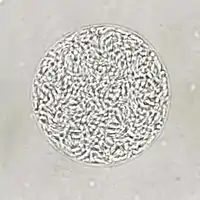

| Giemsa stained T. gondii tachyzoites, 1000× magnification | |

Tachyzoites

Motile, and quickly multiplying, tachyzoites are responsible for expanding the population of the parasite in the host.[45][28]: 19 When a host consumes a tissue cyst (containing bradyzoites) or an oocyst (containing sporozoites), the bradyzoites or sporozoites stage-convert into tachyzoites upon infecting the intestinal epithelium of the host.[28]: 359 During the initial acute period of infection, tachyzoites spread throughout the body via the blood stream.[28]: 39–40 During the later, latent (chronic) stages of infection, tachyzoites stage-convert to bradyzoites to form tissue cysts.